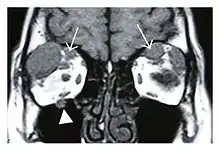

Infraorbital nerve enlargement (IONE) is considered to be a particularly suspicious sign of IgG4-ROD, but seems to occur only when inflammation is in direct contact with the infraorbital canal.[10] IONE is defined as the infraorbital nerve diameter being greater than the optic nerve diameter in the coronal plane.

![]() Bilateral supraorbital nerve enlargements (arrows) and right infraorbital nerve (arrow head) enlargement in a 47-year-old woman with a serum IgG4 of 1000 mg/dL.[1] (T1-weighted MRI) |